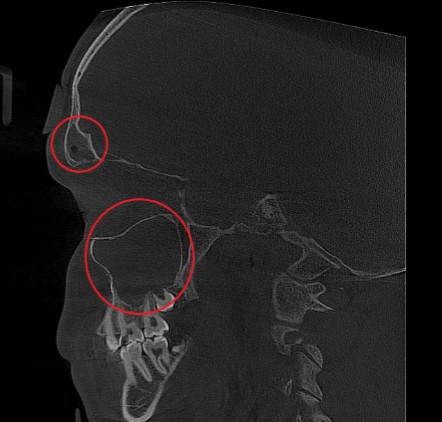

Проведена компьютерная томография околоносовых пазух, которая подтвердила наличие правостороннего гемисинусита (воспаление нескольких пазух с одной стороны), как следствие периодонтита зуба 1.6.

Представлено КЛКТ околоносовых пазух до начала лечения. Выделена зона воспаления пазух.